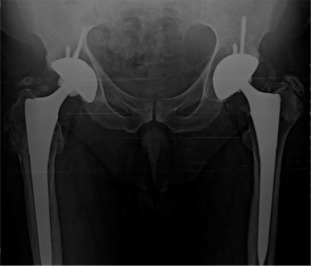

Four years after bilateral simultaneous THA.

Fig. 2.

There were 61 patients (50 male, 11 female) with 105 affected hips (72% bilateral, 28% unilateral). The average patient age at surgery was 41.3 ± 10.2 years old. The age of patients at THA was as follows: <30 years for 14 patients (23 hips), 31–50 years for 41 patients (73 hips) and >50 years for 6 patients (9 hips) (Graph 1 ). The younger age at diagnosis (<30 years old) of AS was correlated with younger age at THA (p < 0.05). Bone ankylosis was detected in 37 (35%) and acetabular protrusion was noticed in 18 (17%) hips in pre-operative radiographs (Fig. 1 , Fig. 2 , Fig. 3  ;  Fig. 4 ) (Table 1 ). The mean pre-operative flexion contracture was 20.3°±21.8°. In patients without ankylosis, the mean total hip range of motion (ROM) was 67.8°±25.7°.